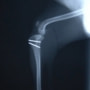

■ 症例20 ポメラニアン 8ヶ月 1.8kg

左右膝蓋骨脱臼 グレードⅢ

2ヶ月前から間欠的跛行が認められ、両膝の膝蓋骨脱臼整復術を行った。

手技は縫工筋及び内側広筋の解放、脛骨粗面の外側転位、滑車ブロック形造溝術、内外側関節包の縫縮を選択し実施した。

右側の膝蓋骨脱臼は上記手技で整復されたものの、左側はそれのみでは膝蓋骨が浮く様子が認められた。その為、PDS縫合糸にて膝蓋靱帯を1糸のみ縫合し、靱帯の縫縮を行った。

膝蓋骨脱臼は膝関節における膝蓋骨の内外側の脱臼と定義されるが、時として単純な内外の脱臼ではなく、膝蓋骨が大きく前方に浮き上がるように脱臼する場合がある。特にトイプードルやポメラニアンといった犬種に多く認められる。

内側脱臼に加えて前方への浮き上がりを矯正する為に、従来より脛骨粗面転移により膝蓋靭帯を外方と下方に引っ張り、固定する方法を選択する。膝蓋骨の前方への浮き上がりが軽度の場合は、従来法ではなく関節包の縫縮で対応していた。しかし、一部の症例で膝蓋骨の動きが悪くなり伸展機構が円滑に機能せずロボット様歩行になるケースがあった。

その為、膝蓋靭帯自体を縫縮する方法を採用した。この方法により、膝関節の伸展機構を妨げず膝蓋骨の軽度の浮きを矯正することが可能となった。

本症例の経過は良好である